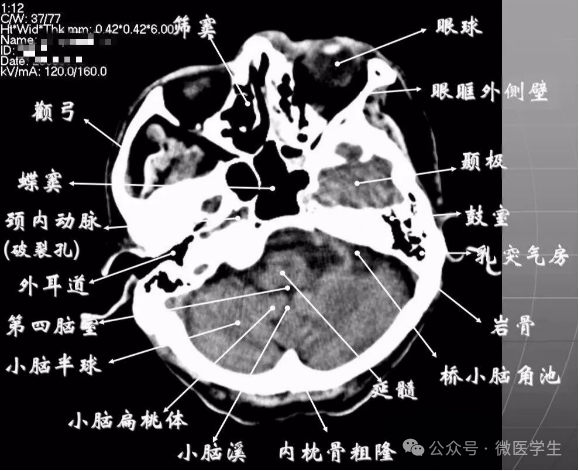

- 颅前窝底部:眼眶,眼球,筛窦,蝶窦,前床突等。

- 颅中窝:前界—蝶骨;后界—颞骨岩部(岩骨);内缘—海绵窦及垂体窝;外缘—颞骨,窝内为颞叶,其内侧为海马回。

- 颅后窝:前缘—岩骨;后缘—枕骨;鞍背后方—脑桥前池,向两侧延伸为脑桥小脑角池。

- 第四脑室:位于颅后窝中线上,后面紧邻小脑蚓部,其两侧为小脑扁桃体。

- 延髓、脑桥:位于第四脑室前。

- 颅前窝:颞叶。

- 鞍上池:在垂体窝上方,位于两侧颅中窝之间,前界为颞叶直回,侧方位颞叶海马,呈五角星形或六角星形。其前角连于纵裂池,两外侧角连于外侧裂池,两后外侧角延续于环池,第六个角位于后缘中间,是角间池。鞍上池边缘为大脑动脉环,池内前部常可见“v”字型视交叉。